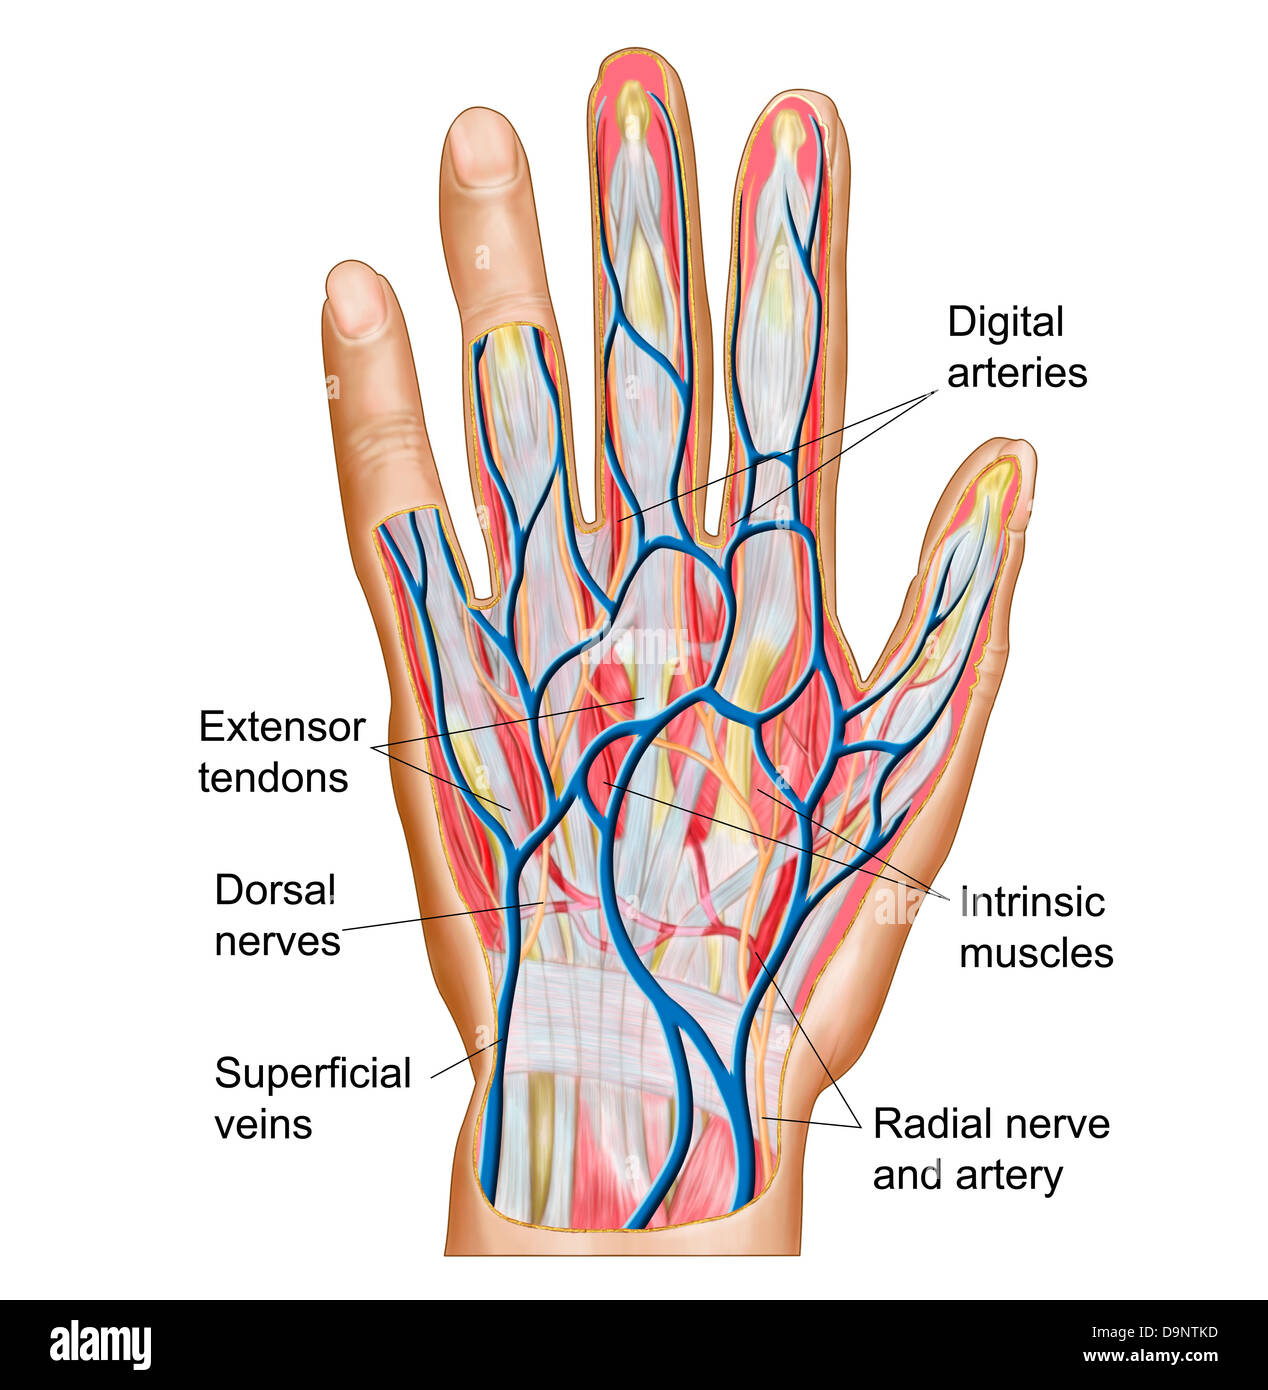

Anatomía del dorso de la mano humana Fotografía de stock Alamy

Anatomía de la mano Fotografía de stock Alamy

Tendones de la mano ligamentos de la mano Imágenes de stock en blanco y negro Alamy